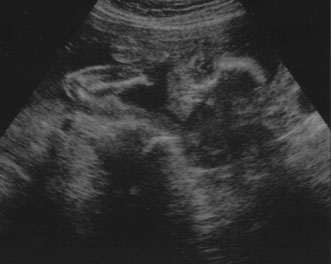

SECOND TRIMESTER ULTRASOUND

A second trimester ultrasound is usually done at 20 to 22 weeks' gestational age. The most commonly used fetal measurements are biparietal diameter, length of the femur or other long bones, and abdominal and head circumference. In addition to measurements, an anatomic survey is also done to evaluate the fetal brain (Fig. 9), spine, stomach, heart, kidneys, placental location and assessment of amniotic fluid (Fig. 10). If maternal risk factors are present, tetra screening results are abnormal, or there are abnormal findings on the anatomic survey, the patient is sent for a comprehensive ultrasound. The components of a comprehensive ultrasound are shown in Table 9. The ultrasound findings associated with Down syndrome include cardiac defects or enlargement, cystic hygroma (Fig. 11), duodenal atresia (Fig. 12), omphalocele, polyhydramnios, choroids plexus cyst, and renal calyceal dilation.

Fig. 9. Transaxial ultrasound of fetal heads.